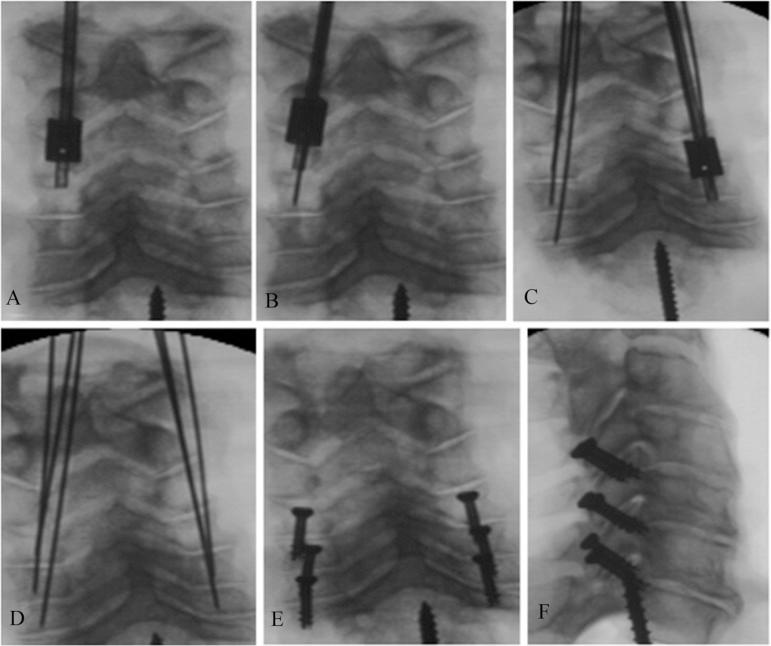

方法

利用先前确定的关节突形态测量法来确定下颈椎经关节突螺钉置入的理想轨迹。开发了一种独特的瞄准导向器,以允许在无侧位透视荧光镜检查引导的情况下将克氏针以90°穿过关节突关节。在7个尸体标本中经皮放置克氏针和空心螺钉。器械置入完全在改良前后位透视荧光镜检查下进行。由2名接受过专科培训的骨科脊柱外科医生使用计算机断层扫描对所有标本的螺钉置入情况进行评估,以确定是否可接受。通过开放解剖来确认影像学解释。可接受的置入定义为螺钉穿过关节突关节,在下关节突和上关节突获得锚定,且不侵犯关键结构。位置不当定义为侵犯横突孔、椎管或神经根或固定不充分。